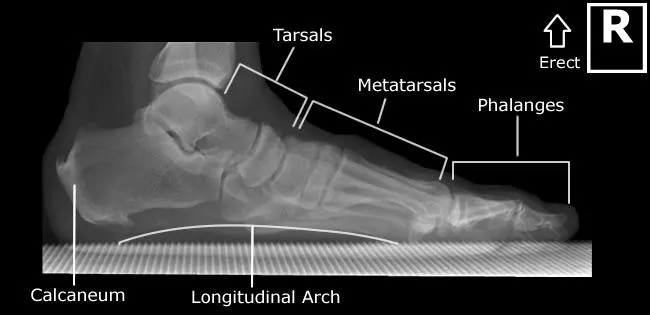

3.重心前移:

這種姿勢會使身體的重心前移到前腳掌,而非後腳跟。這會影響我們的步態,難以有效地用腳跟著地,久而久之可能導致其他問題。